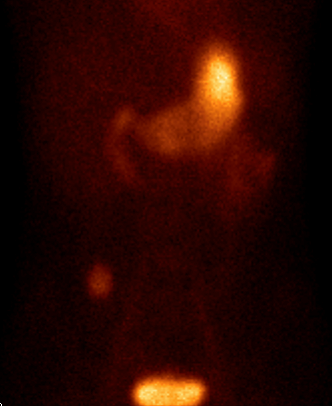

21.4.1.3.2. Somatostatin receptor scintigraphy

Many tumors express somatostatin receptors, especially the various types of neuroendocrine tumors (for example carcinoid, meningeoma, medulloblastoma and neuroblastoma). These can be investigated with somatostatin analogue peptides, most commonly with pentetreotide, an 111In isotope labeled peptide (OctreoScan). This examination is primarily significant in carcinoid and GEP (gastroenteropancreatic) tumor (gastrinoma, insulinoma, glucagonoma, VIPoma) diagnostics. Although GEP tumors present with a severe clinical picture, they are usually small and their detection with other imaging modalities is difficult. For this reason, somatostatin receptor scintigraphy is the recommended method of first choice. If the carcinoid is well differentiated, it is able to detect the lesion and possible metastases. Furthermore, it is useful in therapy monitoring and in cases of planned liver transplantation to rule out extrahepatic metastases. (Figure 13.)

Image

a

b

c

13. Somatostatin receptor scintigraphy (Octreoscan). Planar anterior (a), transversal (b) and coronal (c) fusion SPECT-CT images. Multiplex liver metastases, the primary neuroendocrine tumor is in the head of the pancreas.